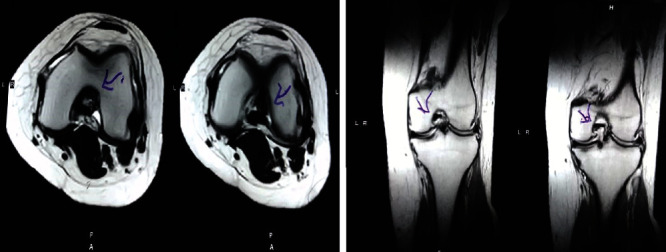

治疗后一个月进行随访。在第一次细胞治疗后,患者的疼痛明显减轻。第二次疗程后,她没有疼痛,并注意到运动范围有所改善。持续的物理治疗也观察到下肢肌肉力量的增加。从治疗开始(11个月前)到最后一次随访(4个月前),患者按照建议的饮食和基于运动的方案减重了11公斤。因此,她现在整体身体健康,能够更舒适地进行日常生活活动。表3显示治疗前后的MRI检查结果。人物的图1和的和图2显示半月板撕裂的治疗前和治疗后(1年后)图片。观察到损伤程度的改善图2。